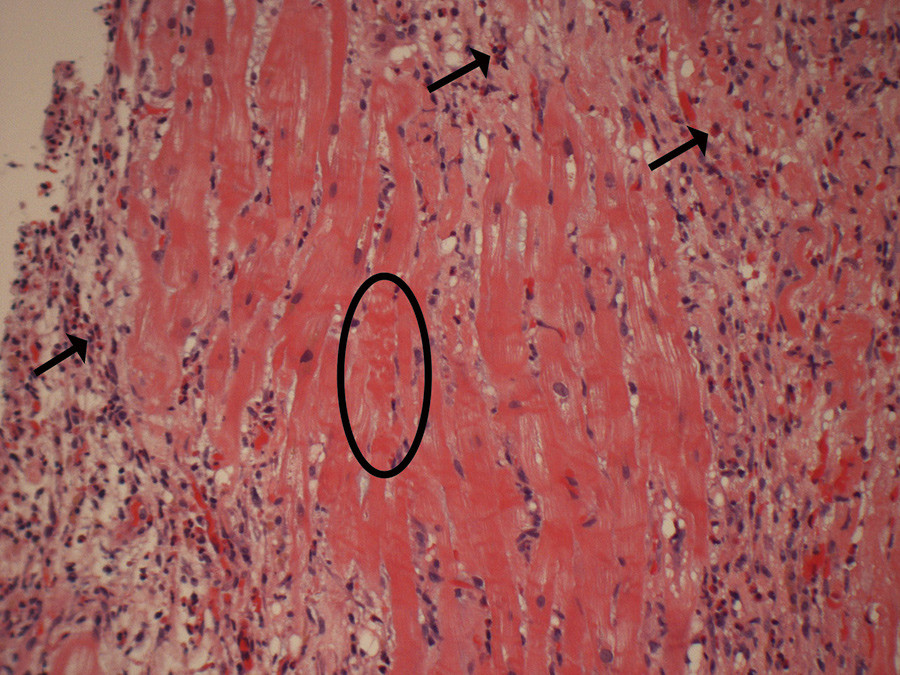

Pasienten pustet lettere allerede samme dag som han fikk sin første dose metylprednisolon, og etter tre doser beskrev han betydelig tilbakegang av alle symptomer. Hudfargen ble bedre, han kjente lukt for første gang på flere år og kunne ligge flatt hele natten gjennom uten dyspné. Hjertebiopsien viste kronisk aktiv betennelse med eosinofile granulocytter og infarktforandringer (e-fig 5). Funnet var forenlig med eosinofil myokarditt med infarktforandringer, slik det er beskrevet ved myokardaffeksjon ved eosinofil granulomatose med polyangiitt.

Nest etter hjerteinfarkt er myokarditt en av de vanligste årsakene til betydelig forhøyede troponinverdier. Myokarditt defineres histologisk ut fra Dallas-kriteriene, men disse har begrenset verdi grunnet prøvetakingsfeil, lav sensitivitet og variabilitet i den histologiske vurderingen (3, 5). Ved positiv hjertebiopsi er myokardittdiagnosen sikker. Komplikasjoner relatert til endomyokardial biopsi er relativt sjeldne (3,3 %), men kan være alvorlige (arytmier, ledningsforstyrrelser og perforasjon) (10). Dette er derfor kun indisert hos pasienter hvor biopsien kan ha konsekvenser for behandlingen og dermed kan påvirke prognosen.

Vår pasient hadde betydelig forhøyet nivå av eosinofile granulocytter i blodet, noe som ledet utredningen inn på hypereosinofile årsaker til myokarditt. Det er flere hypereosinofile tilstander som kan forårsake endomyokardial skade. Disse inkluderer idiopatisk hypereosinofilt syndrom, maligne tilstander, parasittære infeksjoner, vaskulitter og granulomatøse tilstander, tropisk endomyokardial sykdom, medikamentreaksjoner og transplantatrejeksjon (13). Eosinofil infiltrasjon i vev og påfølgende frigjøring av proteiner kan gi direkte vevs- og endotelskade (14).